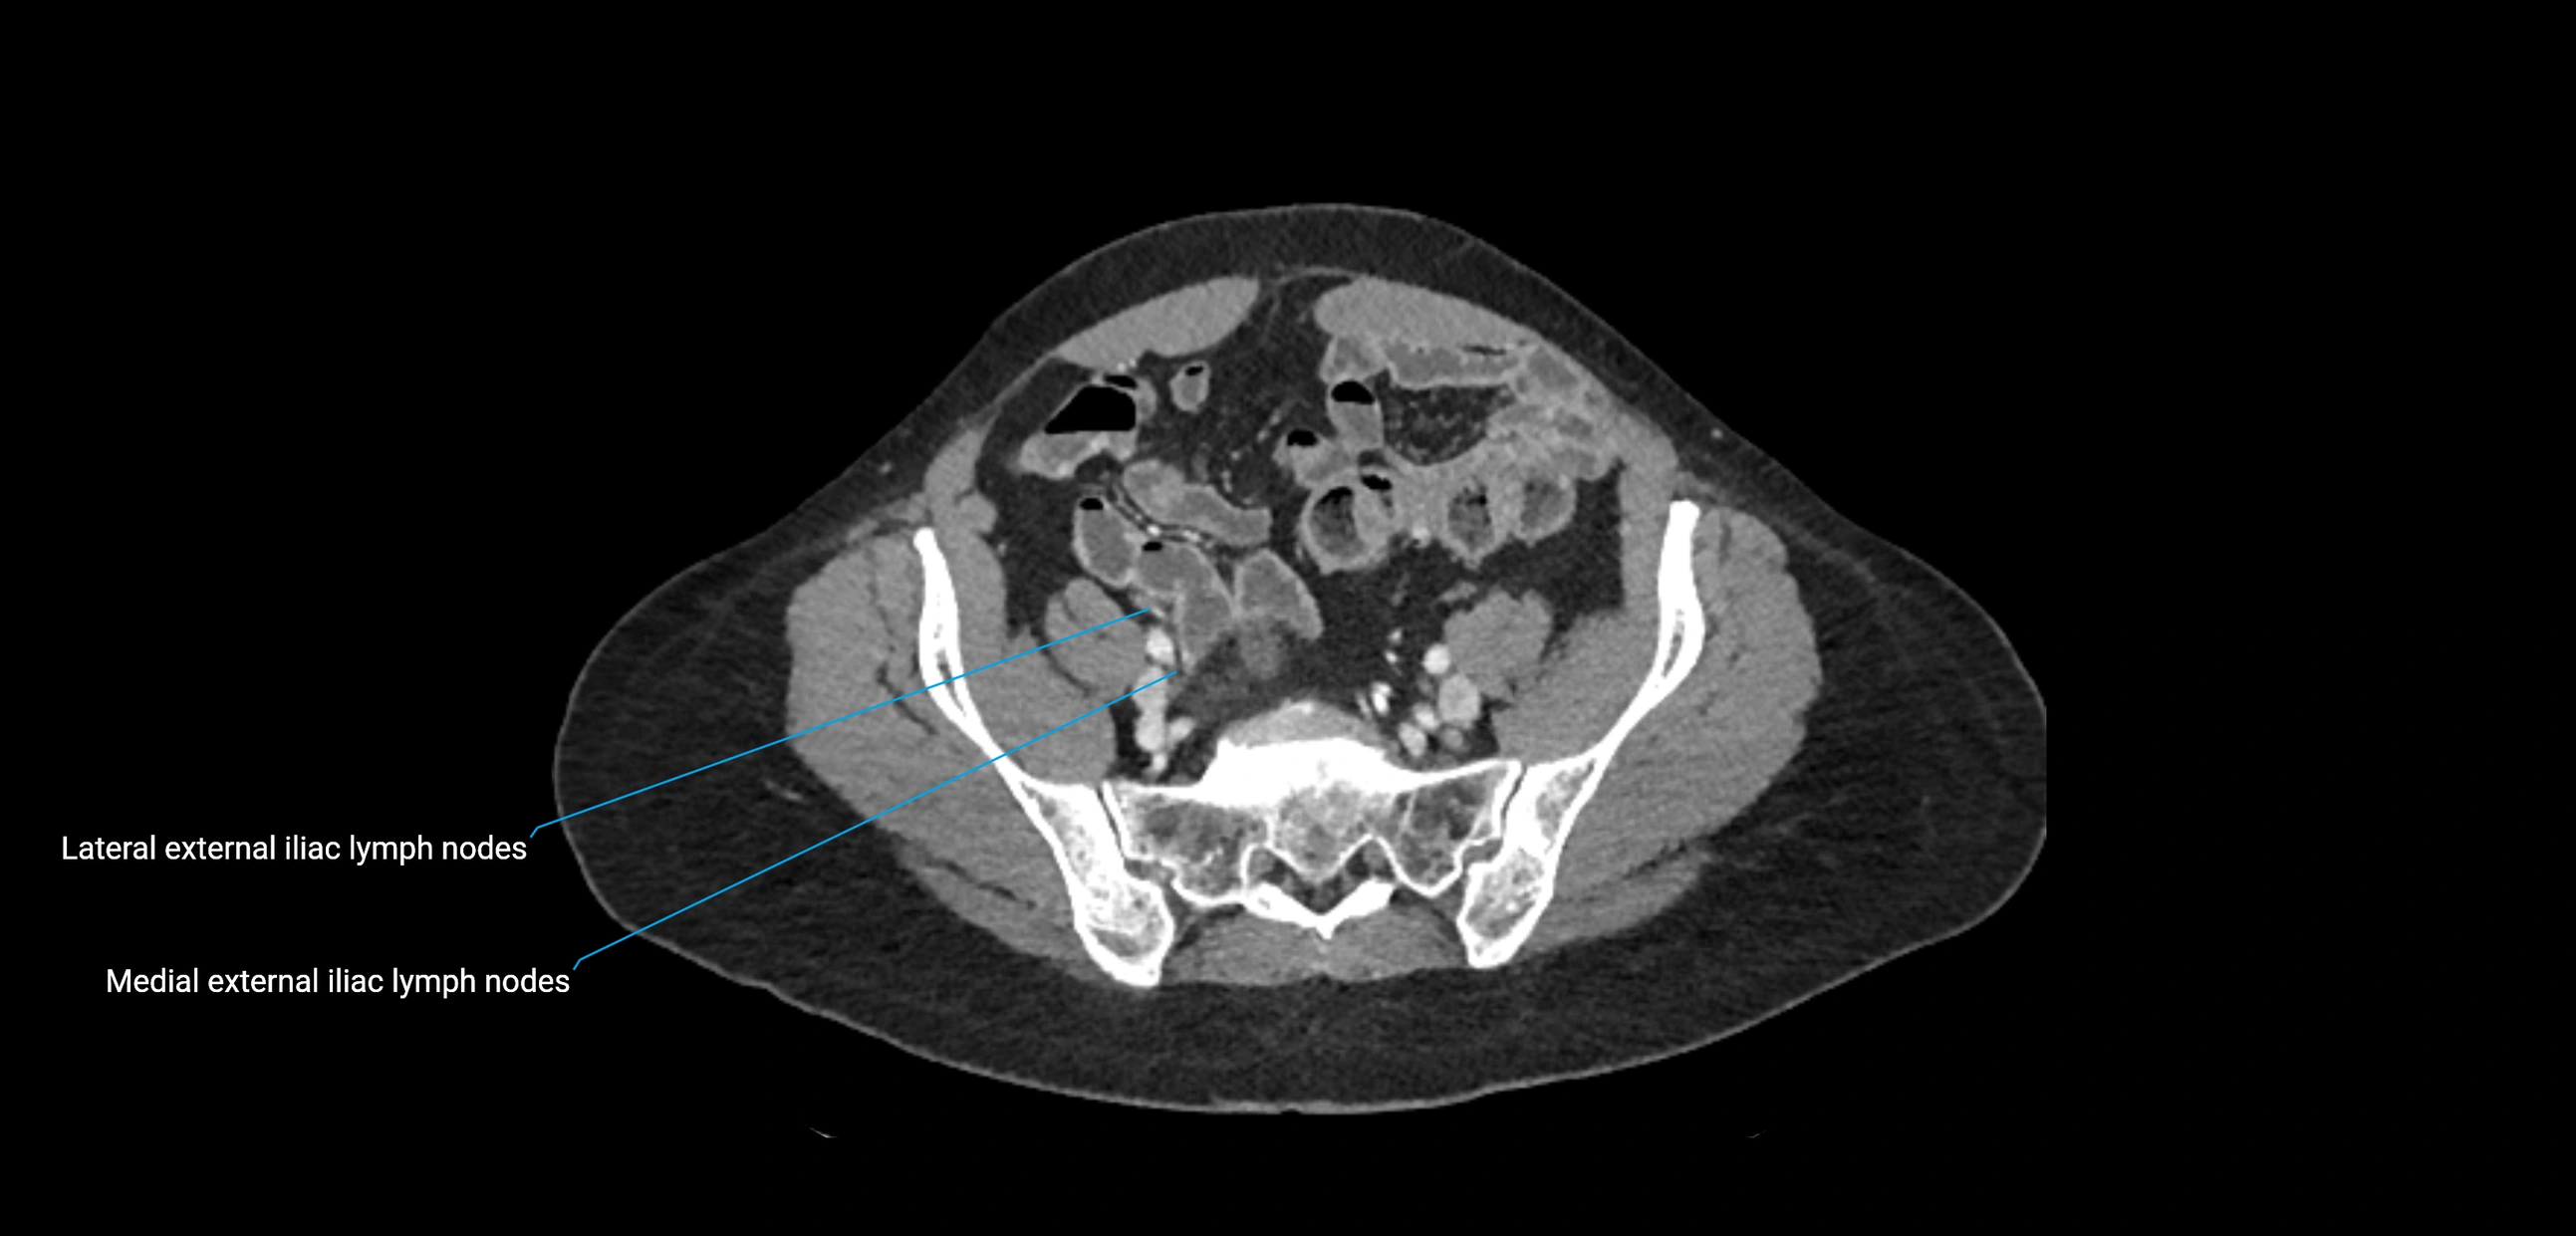

CT Appearance

CT Post-Contrast:

• Normal nodes enhance homogeneously

• Malignant nodes may show heterogeneous enhancement, central necrosis, or conglomerate formation

• Size >1 cm short axis is suspicious, though morphology and distribution are equally important

CT Venography (CTV):

• Demonstrates nodal encasement or compression of adjacent vessels (aorta, IVC, renal veins)

• Useful in staging testicular and ovarian malignancies

• Provides 3D reconstructions for retroperitoneal lymph node dissection planning